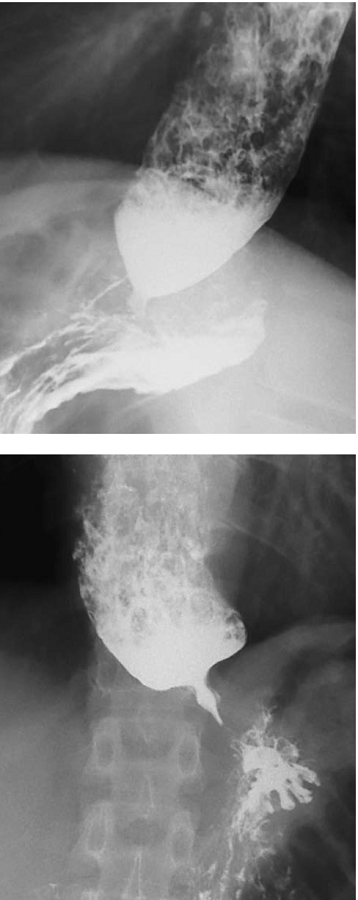

El esofagograma puede mostrar el clásico aspecto de ‘pico de pájaro’, dilatación esofágica y ausencia de peristalsis 12 (figura 1).